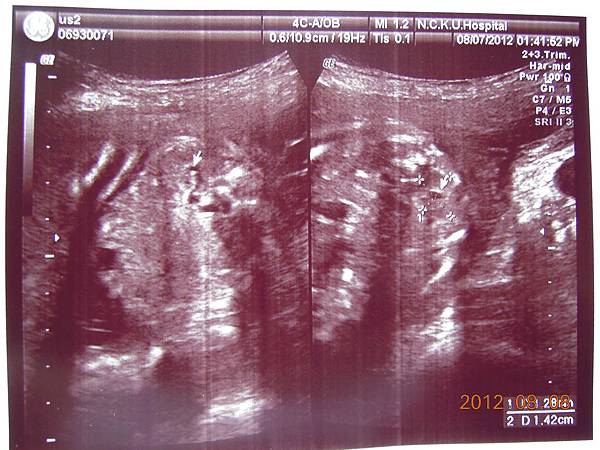

可以看到的是在逼逼的上方剛好被胎盤擋著,比較看不到他的正面,除了肛門無法看到(怕沒有肛門),醫師說現在看不到,小雞雞也沒照他的大小(我怕他發育不良),其他身體器官包括腦部剖有量測他的大小及羊水多寡(我怕像上次一樣羊水太少),今天量出來是12,喔彌陀佛~~

大約檢查了有四五十分鐘,也數了他的手指腳趾,看起來是沒異狀,就叫我等下把報告拿過去門診給游醫師看,還給我ㄧ堆照片,就是下面那些~~

這是他給我的報告,都是一些代號,游醫師說明很快,不過我聽他說沒問題,就比較放心,裡面有把每個器官大約生長到幾週做個說明,大致都在22~24周,逼逼體重約697g~

接下來就是他的一堆檢查照片啦~~